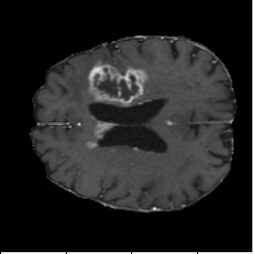

Three-column qualitative comparison: Input, Ground Truth, Prediction.

FNO Baseline (Figure 4, PDF page 8)

DICE 65.13% · Captures global context but loses boundary precision.

Diffusion with U-shape (Figure 5, PDF page 8)

DICE 69.44% · Best qualitative and quantitative segmentation quality.

FNO-Diffusion Hybrid (Figure 6, PDF page 8)

DICE 57.03% · Hybrid underperformed, especially on fine local boundaries.